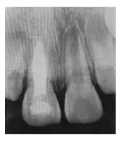

3個月后復診,X線片示:11、21根尖孔未閉合,11根尖部糊劑無明顯吸收,雖根中1/3內(nèi)吸收未見明顯改善,但根尖孔有閉合傾向,牙根長度開始增加,牙根發(fā)育接近8期,同時發(fā)現(xiàn)11根尖閉合程度略高于21,兩者的牙根長度相近(圖1d)。

圖1d 術后3個月X線片

8個月后復診,X線片示:11、21根尖孔未閉合,11根尖部糊劑無明顯吸收,根中1/3內(nèi)吸收未見明顯變化。經(jīng)根尖誘導治療后,11根尖孔閉合程度明顯高于21牙根的自然發(fā)育程度,11發(fā)育接近9期,21發(fā)育8期,兩者牙根長度接近(圖1e)。建議6個月后再復診,待牙根發(fā)育完成、根尖孔閉合后,再完成永久性根管治療。

圖1e 術后8個月X線片